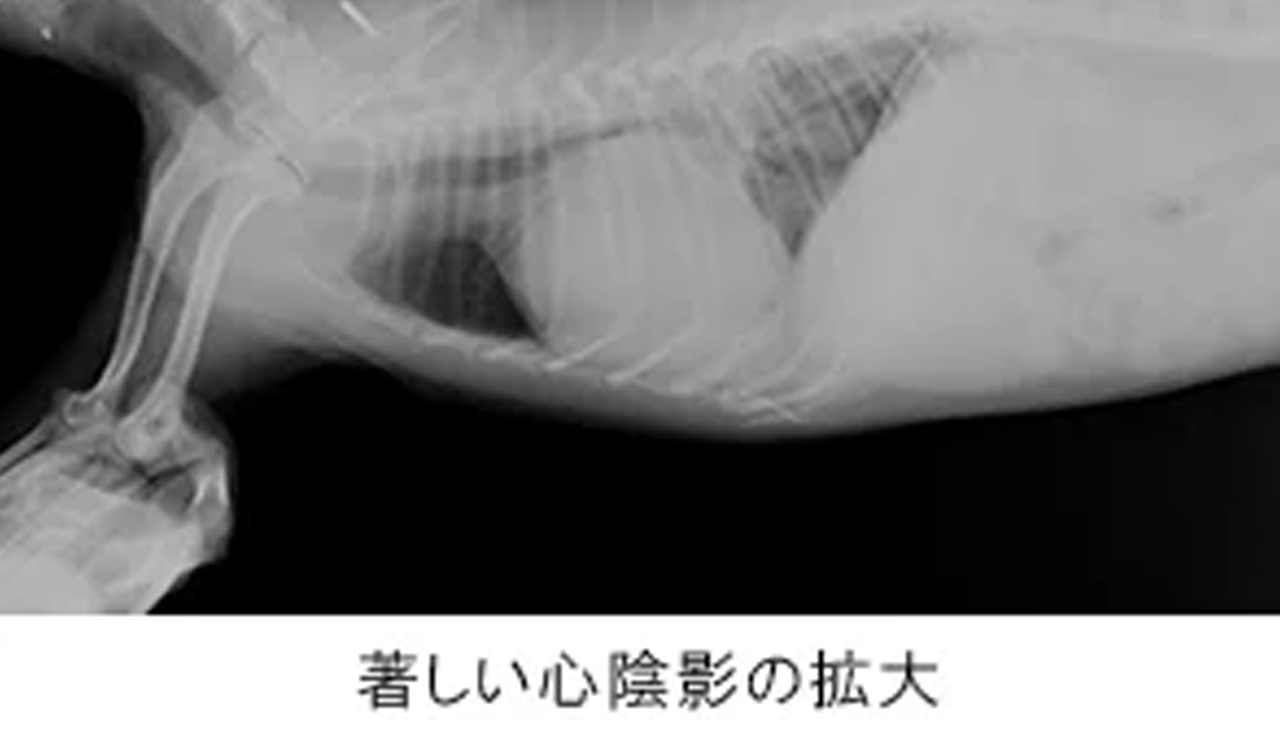

初期には症状が出ないことも多く、精密検査ではじめて発見に至ることも多い動物の心臓病。年齢とともに罹患率も高まり、重篤化しやすいため、定期的な診察を通じて早期発見・早期治療を心がけましょう。

ピジョン動物愛護病院では、各院いずれもレントゲン検査や最新の超音波検査装置による心臓の精密検査を実施しています。

| 痛みを伴うことなく心臓の大きさ・形態や肺の評価を可能にする装置。とくに心不全時に認められる肺水腫の診断に威力を発揮します。 なお、院内には専用のネットワークで機器や各端末が連携しているため、診察室にいながら撮影結果を確認でき、飼い主様への的確なご説明が可能です。 |